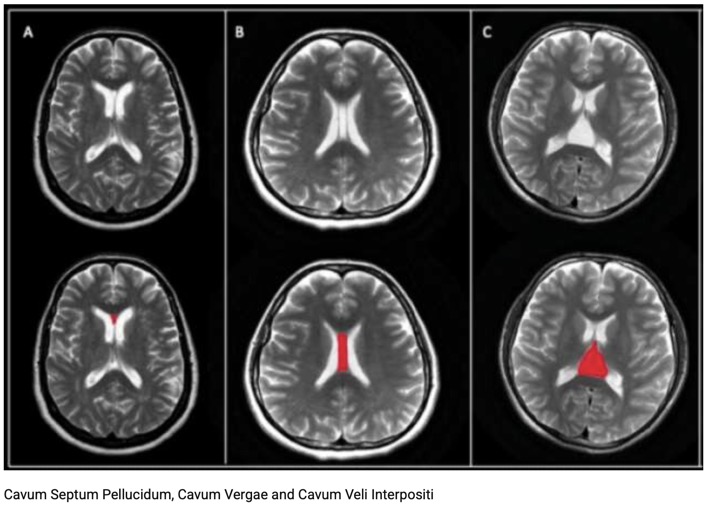

Kystes ligne médiane